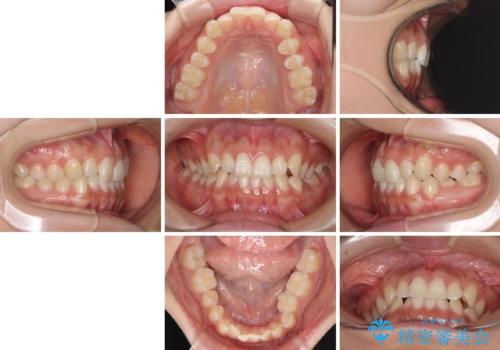

- 前歯の叢生と、奥歯の咬み合わせの悪さを気にして来院された患者様です。

左下には後続永久歯の欠損した乳歯が残存しており、叢生を相まって咬合関係が乱れていました。

乳歯は抜歯し、インビザラインにて矯正治療を行いながら、並行してインプラントによる補綴治療を行うこととしました。